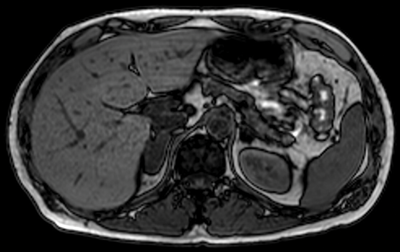

In opposed phase MRI scanning techniques, one image is obtained when the dipoles of the positive ions in fat and water are ‘in-phase’ with each other and another is obtained when the dipoles are ‘out of phase’ with each other. These two images can then be processed to assess for the presence of microscopic (intracytoplasmic) fat. On in-phase imaging, adrenal lesions tend to be iso-intense to the spleen. On opposed phase imaging, adrenal lesions containing microscopic fat will lose signal relative to the spleen. This is seen with adrenal adenomas and not with adrenal metastases (Figure 5).

Figure 5:

Top: MRI in-phase.

Bottom: MRI out-of-phase demonstrating loss of signal in left adrenal lesion in keeping

with an adenoma, but no loss of signal in the right adrenal lesion, due to metastasis.